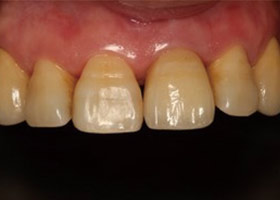

治療前門牙特寫、切端特寫照,發現假牙略微暴牙。

假牙完成後,門牙特寫、切端特寫照,暴牙已不復見。